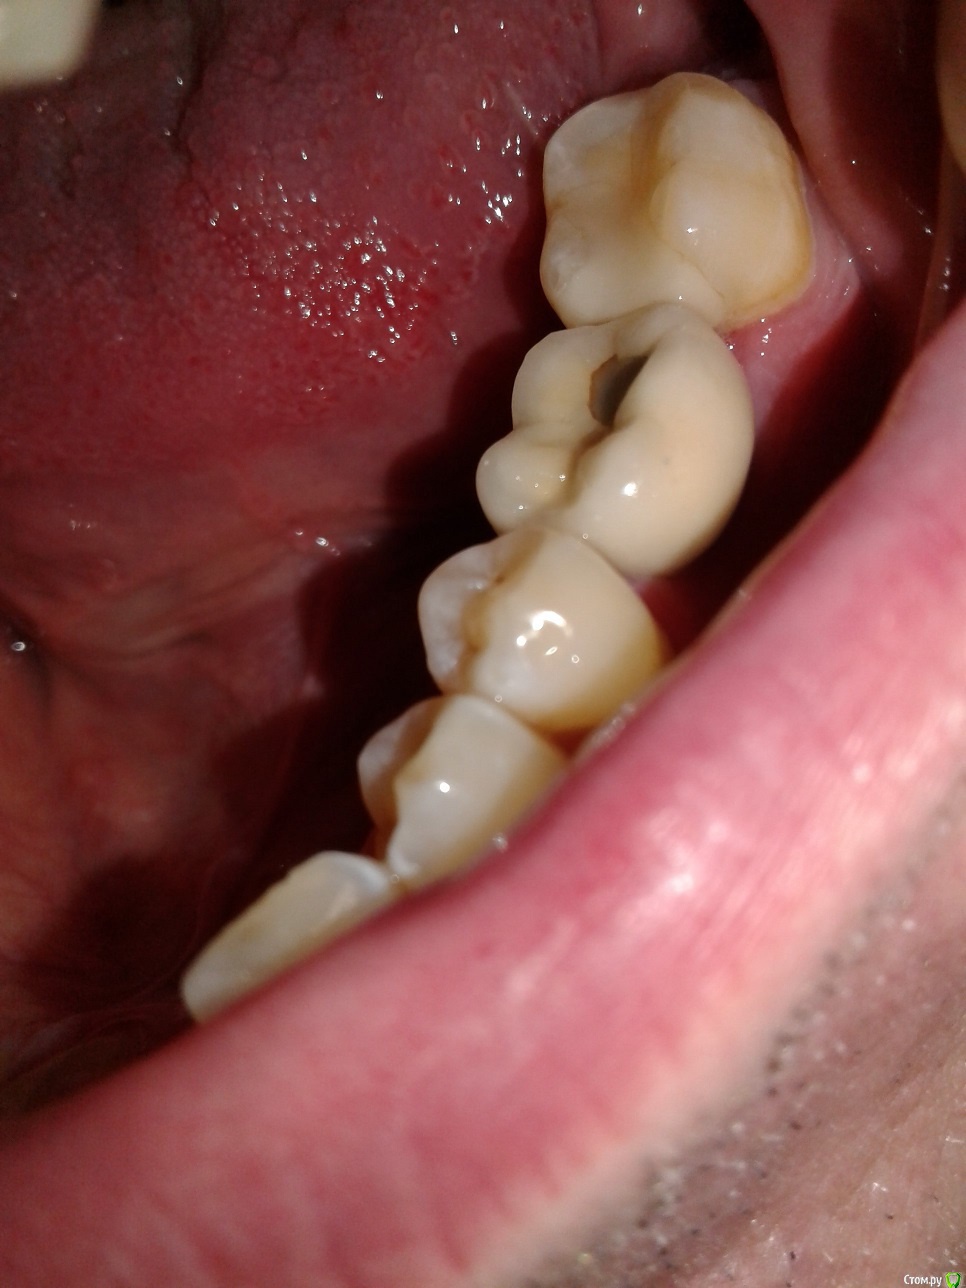

AndyAndy Опубликовано 17 октября, 2019 Поделиться Опубликовано 17 октября, 2019 Пища попадает сверху между коронкой и зубами или сбоку? Проверьте зубной нитью, проваливается она или есть сопротивление. Если дело в слабом контакте, этот вопрос решается заменой/коррекцией коронки, пока не вижу причин менять непосредственно имплантат. Фото во рту можете сделать? Ссылка на комментарий

vad Опубликовано 17 октября, 2019 Автор Поделиться Опубликовано 17 октября, 2019 (изменено) "коронки", конечно.Нити оказывается сопротивление, меньше чем между другими зубами (там еле лезет).Пища попадает спереди и сзади в щель между зубами, и между ними влазит деревянная зубная палочка. Изменено 17 октября, 2019 пользователем vad Ссылка на комментарий

AndyAndy Опубликовано 17 октября, 2019 Поделиться Опубликовано 17 октября, 2019 Зубочистку категорически не рекомендую к использованию, она только усугубляет ситуацию. Надо уплотнять контакты на коронках (замена или коррекция существующих по возможности) Ссылка на комментарий

dentikl Опубликовано 18 октября, 2019 Поделиться Опубликовано 18 октября, 2019 А разве можно эти как-то скорретировать?Мне предлагают только замену за 35 тыр. каждую.Хотелось бы также понять, почему это произошло и как не попасть в такую же ситуацию еще раз.2 пломбы(коронки) на соседние зубы Ссылка на комментарий

vad Опубликовано 18 октября, 2019 Автор Поделиться Опубликовано 18 октября, 2019 (изменено) Замена пломб мне больше нравится и гораздо дешевле.А что реально поможет?Там получаются карманы ближе к корню зуба, получается пломбы нужно прям до десны делать? Изменено 18 октября, 2019 пользователем vad Ссылка на комментарий

red_butler Опубликовано 18 октября, 2019 Поделиться Опубликовано 18 октября, 2019 Покажите фото во рту и обычный панорамный снимок Ссылка на комментарий